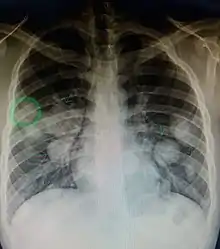

Cut surface of a liver showing multiple paler metastatic nodules originating from pancreatic cancer

Initially, nearby lymph nodes are struck early.[9] The lungs, liver, brain, and bones are the most common metastasis locations from solid tumors.[9]